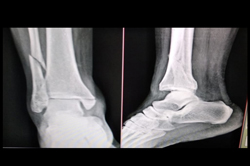

Ankle